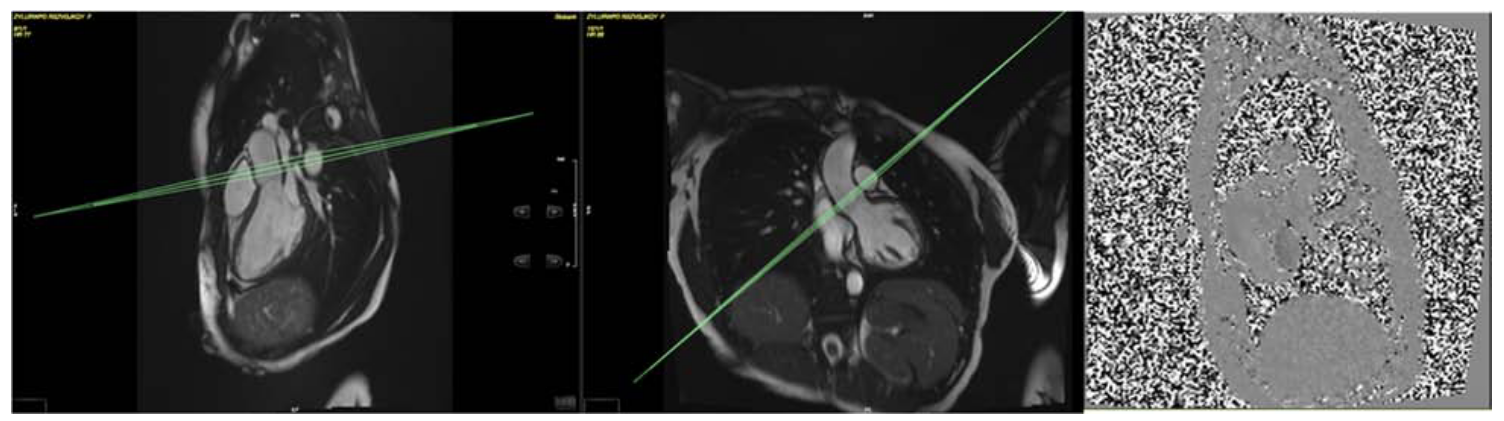

A phase contrast sequence is planned on both sagittal and coronal LVOT cines to capture aortic flow and the number of valve cusps. The plane is located at or immediately above the sino-tubular junction at end diastole. The standard velocity encoding (VENC) is 2 m/s but is adjusted upwards based on presence/degree of turbulence seen on the LVOT cines and if time allows. (Petersen et al., 2015)